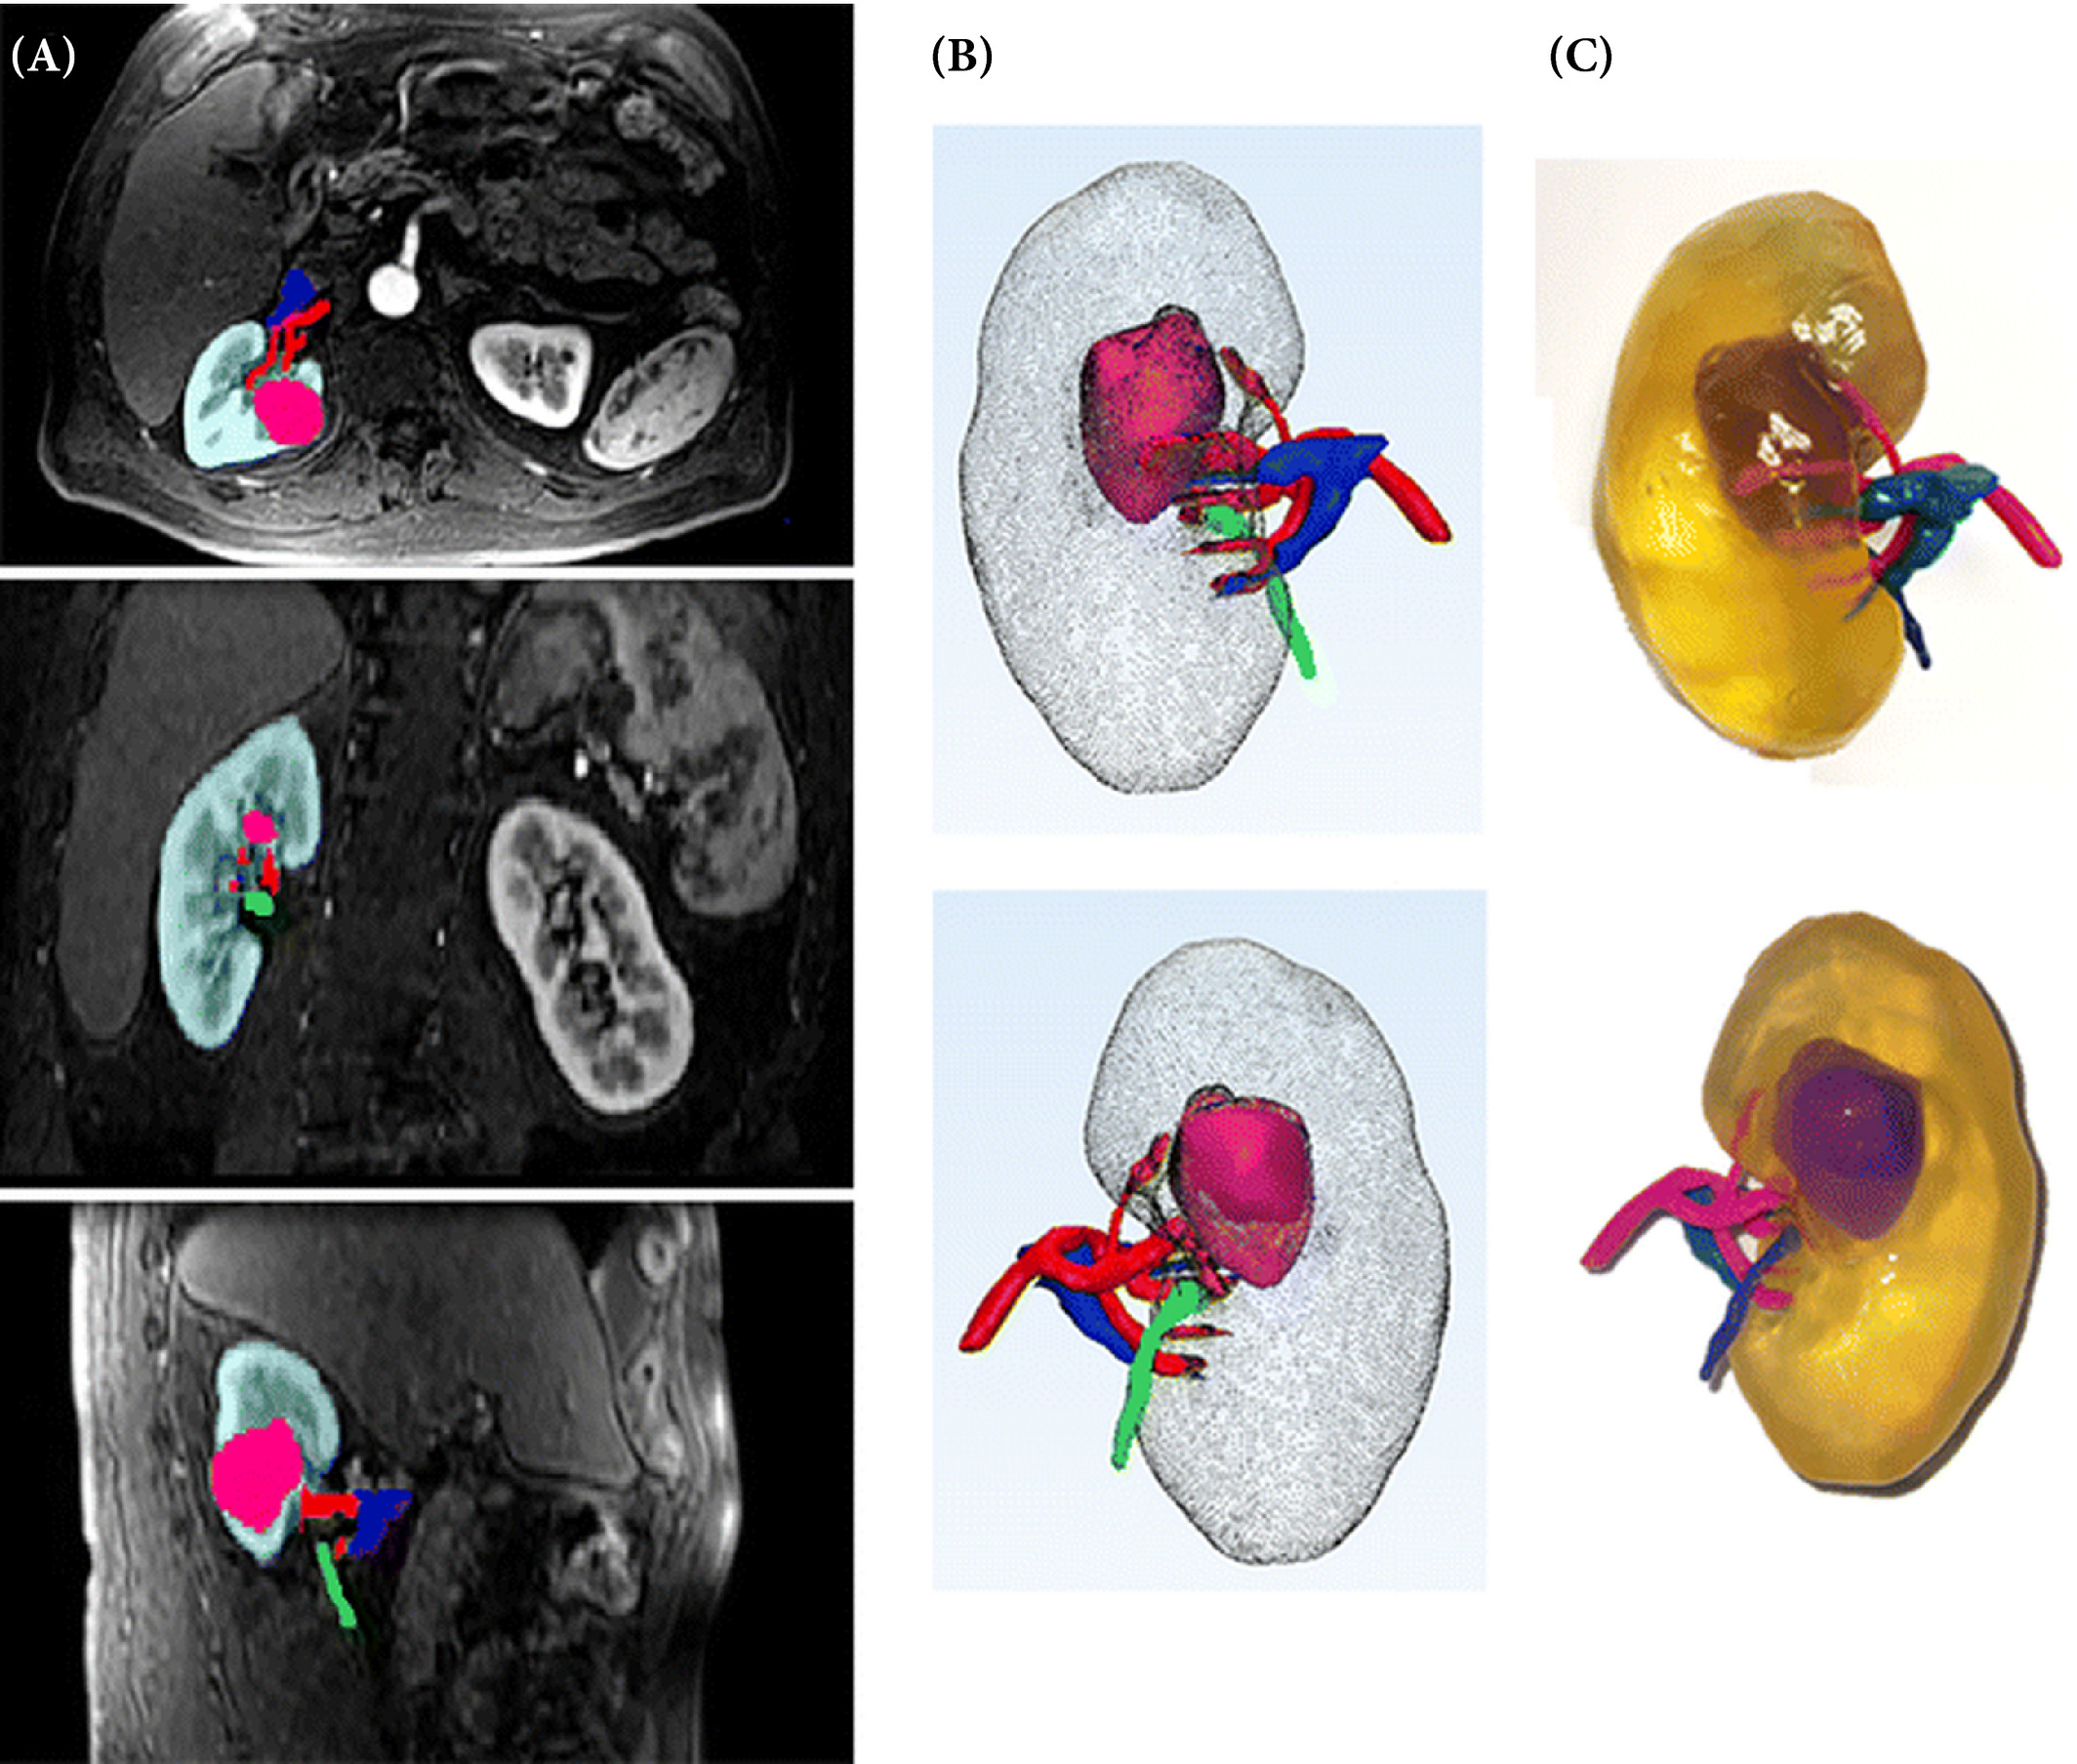

2D and 3D anatomy scans can be used to create a precise, personalized model of a patient’s organ. This model can then be sliced and a low-cost print can be fabricated in-house by the medical personnel. Looking at 3D printed kidney models, Knoedler et al. attempted to use 3D printing to improve medical students’ understanding and accuracy when diagnosing malignant tumors. A set of first-year medical students were given CT scans and 3D printed models of cancerous kidneys as resources. When asked to diagnose the kidneys with the help of the 3D printed models, the researchers found that the assessments improved in three of four metrics of the R.E.N.A.L. nephrometry score when compared to CT scans alone (radius, nearness to collecting system, and location).